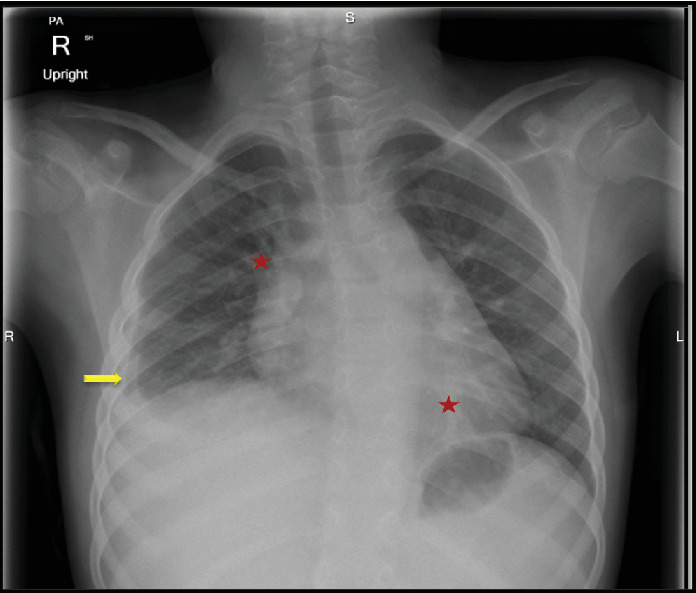

家族性地中海热(FMF)和克罗恩病(CD)是两种具有相似临床和生物学特征的慢性自身炎症性疾病。这两种疾病的特点都是慢性和复发性症状。在某些情况下,FMF可以与乳糜泻共存,这使得诊断和治疗具有挑战性。病例介绍:一名9岁的埃及儿童在5岁时根据临床症状和内窥镜组织病理学检查结果被诊断为乳糜泻。最初,患者对生物治疗(抗tnf α)反应良好,症状改善,炎症标志物和粪便钙保护蛋白水平下降。7岁时,患儿开始出现频繁发热并伴有胸膜炎性胸痛。多次胸部x光检查发现右侧胸腔积液。由于免疫抑制,患者被诊断为复发性急性细菌性肺炎,并接受了多个疗程的口服抗生素治疗。在最后一次报告中,在其中一次发作中,由于对抗生素缺乏反应,持续升高的炎症标志物(CRP, ESR)和无法解决的轻度右侧胸腔积液,因此进行了进一步的调查。根据患者的临床表现和胸部影像学,怀疑为FMF。详细的家族史显示,一位一级表亲有FMF阳性诊断。进行基因检测,发现两个杂合致病突变,支持FMF诊断。秋水仙碱治疗可防止进一步发作。患者继续接受胃肠道小组对CD的随访护理,并维持阿达木单抗。结论:对于表现出肺部症状且对乳糜泻治疗无反应的乳糜泻患儿,应考虑FMF。

Introduction: Familial Mediterranean fever (FMF) and Crohn's disease (CD) are chronic autoinflammatory disorders that share similar clinical and biological features. Both disorders are characterized by chronic and relapsing symptoms. In some cases, FMF can coexist with CD, which makes diagnosis and treatment challenging. Case Presentation: A 9-year-old Egyptian child was diagnosed with CD at the age of 5, based on clinical symptoms and endoscopic histopathologic findings. Initially, the patient responded well to biological therapy (anti-TNFα), showing improvements in symptoms along with declines in inflammatory markers and fecal calprotectin levels. At the age of 7, the child began experiencing frequent episodes of fever accompanied by pleuritic chest pain. Right-sided pleural effusion was identified on repeated chest X-rays. The patient was diagnosed with recurrent acute bacterial pneumonia due to immune suppression and was managed with multiple courses of oral antibiotics. During the last presentation, in one of these episodes, further investigation was pursued due to a lack of response to antibiotics, indicated by persistently elevated inflammatory markers (CRP, ESR) and nonresolving mild right-sided pleural effusion. FMF was suspected based on the patient's clinical presentation and chest imaging. A detailed family history revealed a positive FMF diagnosis in a first-degree cousin. Genetic testing was performed, which revealed two heterozygous pathogenic mutations that support the FMF diagnosis. Treatment with colchicine prevented further episodes. The patient continued to receive follow-up care from the GI team for CD and was maintained on adalimumab. Conclusions: FMF should be considered for children with CD who exhibit pulmonary symptoms that do not respond to CD treatment.